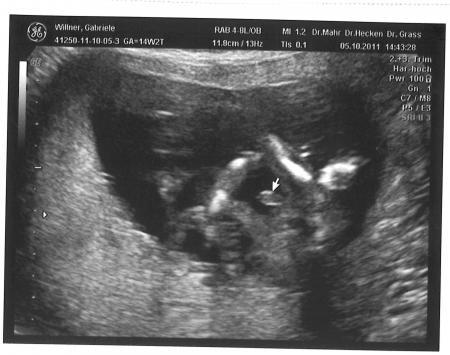

Hallo Dana, ja ich glaube das wird bei mir auch so sein. Der ist sich so sicher, aber ich glaube nicht den Penis zu sehen sondern die Nabelschnur! Siehe Foto. Weil das rechts daneben ist eher ein Arm als ein Bein. LG

Mmmmm, sieht jetzt auch nicht wie ein Penis aus. Das währe sehr groß,oder???

Haha das ist doch niemals ein Schniedi... so groß sind die bei Babys überhaupt nicht. Auch sollte er`s vom Papa haben haha das würde sich erst in der Pubertät zeigen und nicht schon als Baby :D. Ich denke auch das wird auf jedenfall was anderes sein als der Schniedel, sicher eher die Nabelschnur...

Das ist definitiv nicht das Schniedelchen! :-) ..aber ich finde trotzdem, dass man etwas zwischen den Beinen sieht (da wo die Beine wirklich sind) - nur festlegen würde ich mich nicht, da das sehr schwer auf einem einzelnen Bild zu beurteilen ist..